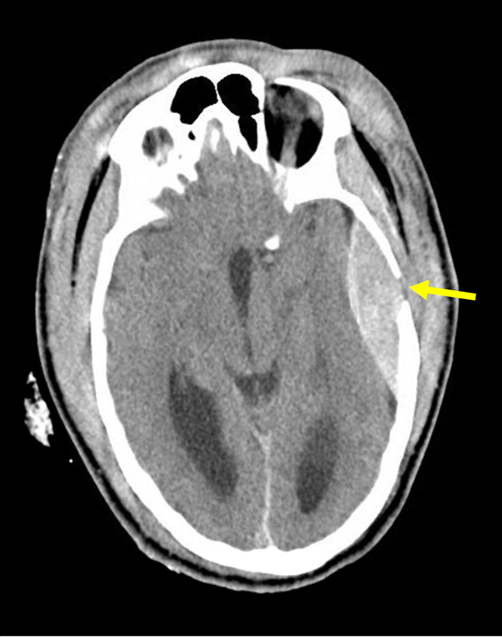

Image credit: Increased Intracranial Pressure Team-Based Learning Module.  Barratt DM, Mader Jr EC, Oliva AA.  MedEdPORTAL Publications; 2015.